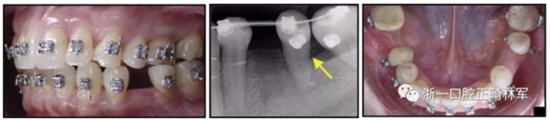

圖10.經(jīng)過(guò)7個(gè)月后,以每月1毫米的速度牽引下頜左側(cè)第二前磨牙,正畸產(chǎn)生的種植部位長(zhǎng)約7毫米。通過(guò)使用固定矯治器保持間隙6個(gè)月。根尖X線(xiàn)片顯示第二前磨僅有少量牙根遠(yuǎn)中面吸收。

經(jīng)過(guò)32個(gè)月的活動(dòng)治療后,上下牙弓排齊良好,下頜第一磨牙區(qū)的雙側(cè)牙間隙可用于種植(圖12,A和13,A)。

圖12.將種植體植入正畸產(chǎn)生的間隙中的步驟:A,將下頜左側(cè)第二前磨牙向遠(yuǎn)中移動(dòng)以在前磨牙之間產(chǎn)生間隙; B,種植部位的咬合面觀(guān); C,一個(gè)水平切口和兩個(gè)垂直切口,距相鄰牙齒1.5mm的距離; D,暴露的牙槽嵴的咬合面觀(guān); E,測(cè)量牙槽嵴的寬度約6mm; F,手術(shù)導(dǎo)板顯示預(yù)備冠頸部的位置距離骨牙槽嵴頂僅1毫米; G,用球鉆修整牙槽嵴; H,建立3mm從手術(shù)導(dǎo)板的頸部輪廓到骨嵴的距離,以實(shí)現(xiàn)必要的生物學(xué)寬度; I,引導(dǎo)針顯示了截骨的角度; J,3.5×10mm種植體完全置于骨內(nèi); K,一個(gè)覆蓋螺帽就位; 和L,縫合。